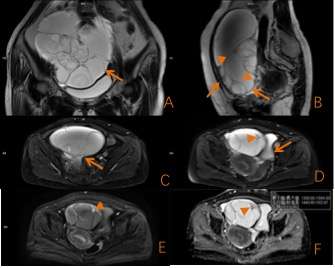

圖3 右側卵巢交界性黏液性囊腺瘤 囊內分隔多見,分隔厚薄不均,局部可見壁結節,DWI呈高信號(箭頭)。